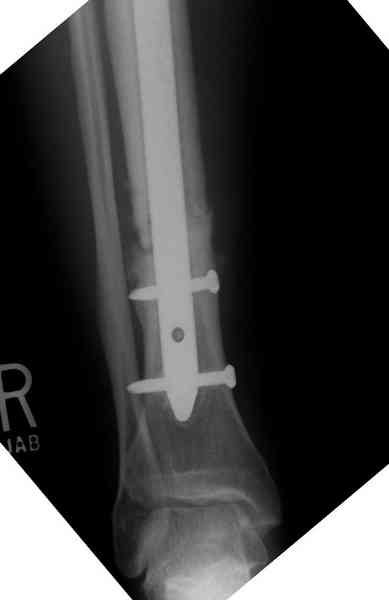

Недавно на нашей ежемесячной Morbidity&Mortality

conference мы разбирали похожий случай, ложный сустав большеберцовой кости после резекции опухоли.

Оперирован в военном госпитале с заменой сегмента

аллокостью большеберцовой кости и после демобилизации явился для постоянного наблюдения по месту жительства.

Наши имели проблему со сращением, пришлось им сделать динамизацию, дополнительную аутопластику.

Снимки представлены.